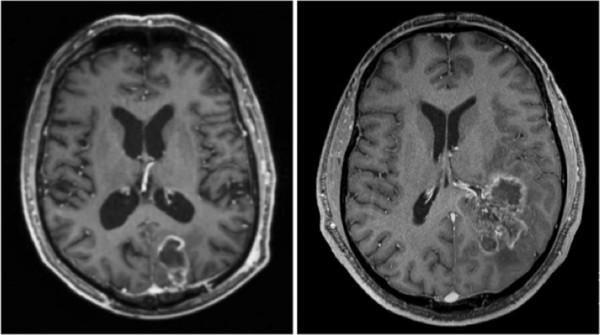

Glioblastoma (GBM) is one of the primary malignant brain tumors derived from glial cells of the central nervous system (Figure 1) Glial cells are responsible for supporting neuronal function, so one can imagine that uncontrolled growth of these cells can lead to serious neurological consequences affecting the functional processes of the brain GBMs originate from astrocytes and masses are found within cerebral hemispheres, as a “butterfly glioma” crossing the corpus callosum (Figure 2) In histopathological slides, GBMs present as poorly differentiated primitive cells with pseudopalisading necrosis (Figure 3)

Figure 2. Coronal T1 MRI of a typical “butterfly glioma”

Johnston et al. found that pre-diagnostic MRI analysis of T1 images demonstrated hypointense lesions in LTS patients, with STS presenting with mixed-intensity lesions Gray matter involvement was mostly common in STS patients, but it is not a determinant characteristic and further imaging should be carried out T2/FLAIR hyperintensity was more common in LTS while there were no differences in T2/FLAIR heterogeneous signals between both groups One of the most significant results by show that contrast enhancement is significantly more prominent in wild-type IDH GBM patients Wang et al found that radiological features combined with IDH1 status for predicting the survival outcome of GBM patients showed that tumor contrast enhancement, multi-enhancing foci, and peritumoral edema, were found to be associated with the survival outcomes of GBM patients with IDH mutations.

Image credits: Cover Image – Adapted from Adeberg S, Bostel T, König L, Welzel T, Debus J, Combs SE A comparison of long-term survivors and short-term survivors with glioblastoma, subventricular zone involvement: a predictive factor for survival? Radiat Oncol 2014 Apr 23;9:95 doi: 101186/1748-717X-9-95

Figure 1 – (Blausencom staff (2014) “Medical gallery of Blausen Medical 2014“ WikiJournal ofMedicine 1 (2) DOI:10.15347/wjm/2014.010 ISSN 2002-4436 – Own work)

Figure 2 – Adapted from https://radiopaedia.org/articles/butterflyglioma?lang=us